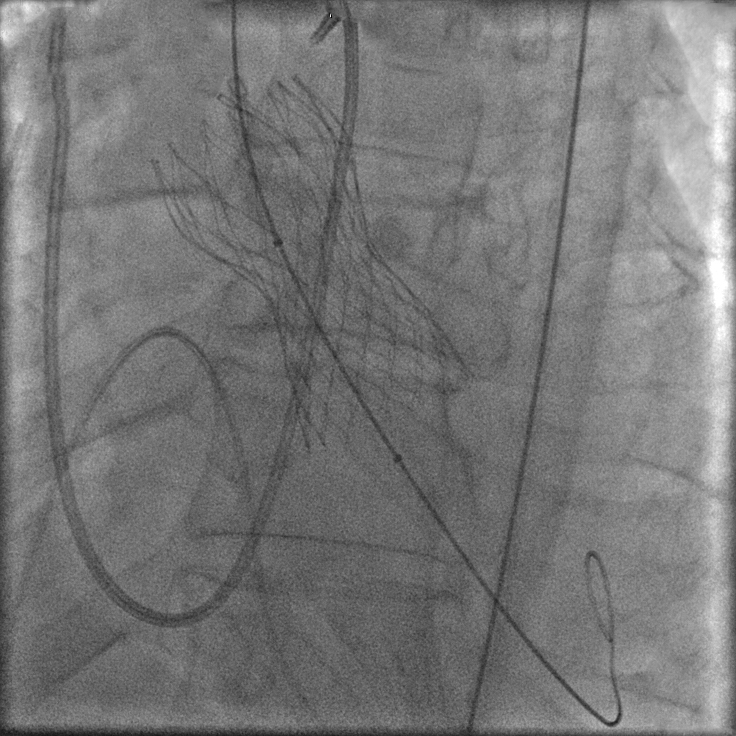

Apoi se introduce pe cale endovasculară, până la nivelul valvei predilatate, o proteză valvulară strânsă în interiorul unei teci. (fig. 3). Proteza valvulară biologică este constituită din ţesuturi de origine animală.

Prin retragerea controlată a tecii, valva se autoexpandează deoarece este inserată pe un schelet metalic de nitiol (fig. 4). Proteza conţine în interiorul scheletului metalic o valvă sintetică nouă, asemănătoare ca structură și funcţie cu cea sănătoasă.

Imaginile prin care sunt ilustrate etapele de implantare a unei proteze valvulare aortice sunt preluate de la primul pacient, în vârstă de 62 de ani, care a depășit cu succes această procedură în Laboratorul de Cardiologie Intervenţională al Spitalului Monza, în luna februarie 2013.